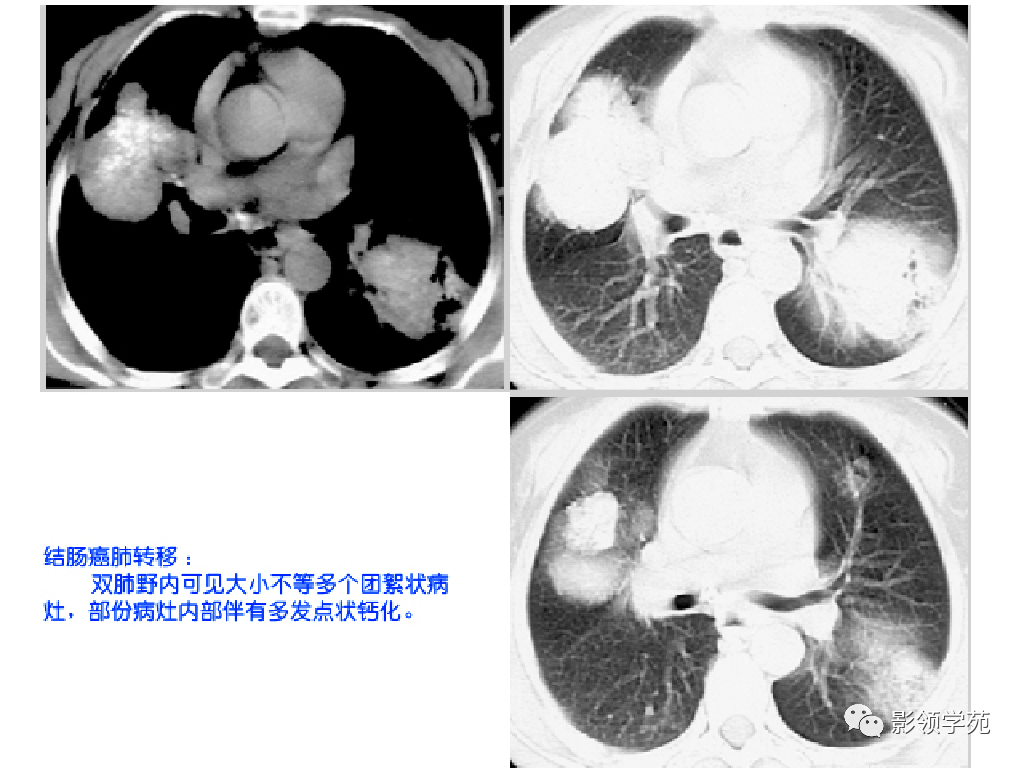

1. 血行性转移 :多发或单发结节,大小不一,边缘较清楚。少数结节伴出血时出现晕轮征,即有略高密度影像环绕结节,使病变边缘模糊。病变有钙化常见于骨肉瘤或软骨肉瘤转移。转移瘤亦可表现为空洞。两肺多发的小结节影具有随机分布的特点,HRCT显示结节位于小叶中心、小叶间隔、支气管血管束及胸膜,结节大小不均匀。

CT诊断:甲状腺癌双肺多发转移

额骨骨纤维肉瘤并肺部转移